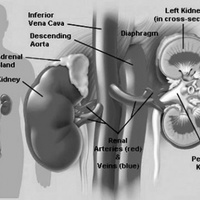

Мочевые органы и половые железы закладываются независимо друг от друга, но при дальнейшем развитии они формируют анатомически единую систему органов.Аномалии развития мочеполовых органов составляют более 30 % всех врожденных пороков развития.

Все аномалии развития почек создают условия для нарушения уродинамики, стаза мочи, инфицирования и развития тяжелых осложнений. Наиболее тяжелым осложнением у детей является пиелонефрит, при поздней диагностике которого развиваются деструктивные изменения в почке. Именно поэтому актуальными становятся ранняя диагностика и своевременная коррекция пороков развития органов мочеполовой системы.